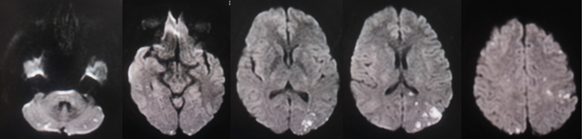

我们来看我院诊治一病例,住院患者女,48岁,3年余前肺穿刺确诊肺腺癌伴肺内转移,行靶向治疗,一年前患左下肢深静脉血栓、双肺肺栓塞于我院行下腔静脉滤器植入+左下肢静脉造影+取栓+球囊扩张术。近日就诊,主诉肢体无力,反应迟钝、记忆错乱2天来就诊。头颅检查如下:

上图所示MRA可见脑动脉未见明显异常,未见狭窄与斑块。DWI所见:双侧小脑半球、胼胝体压部、双侧额顶枕叶多发急性、亚急性梗死。结合临床病史,考虑特鲁索综合征。

头部 DWI 散性分布的急性脑梗死病灶,同时累及前后循环或双侧前循环,或大于三个血管区域的多发性脑梗死;血管成像未见责任动脉狭窄。“三流域征”(Three Territory Sign,TTS),即病变部位累及单侧或双侧(双侧多见)前、后循环,包括3个或3个以上血管分布区域,病变多呈无强化、非环形、聚集成团或单一部位的MRI弥散加权成像(DWI)高信号,直径约0.5~2.0mm,以小梗死灶为主,单纯大面积梗死少见,多位于双侧大脑半球及小脑半球皮质、皮质下或深部白质区,分水岭少见,无弥漫皮质带状或深部灰质核团受累。“三流域征”是恶性肿瘤相关的缺血性脑梗死最引人注目的磁共振影像特征。